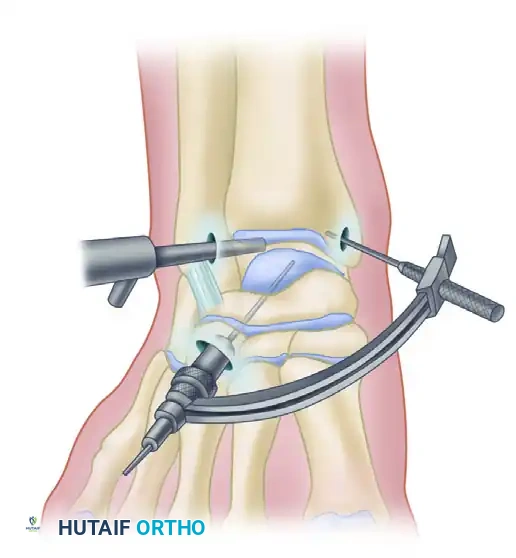

Arthroscopic retrograde drilling and bone grafting as described by Stone and Gould. (A) A guide pin is placed through the sinus tarsi using a modified ligament guide. (B) Graft material is compressed into the channel.

3. Fluoroscopic Confirmation: Intraoperative C-arm fluoroscopy confirms the trajectory and depth.

4. Decompression and Grafting: The tract is over-drilled. The cystic contents are curetted. To prevent articular collapse, the void is backfilled. Options include cancellous autograft, surgical-grade calcium sulfate, or bone marrow aspirate concentrate (BMAC) harvested from the iliac crest.